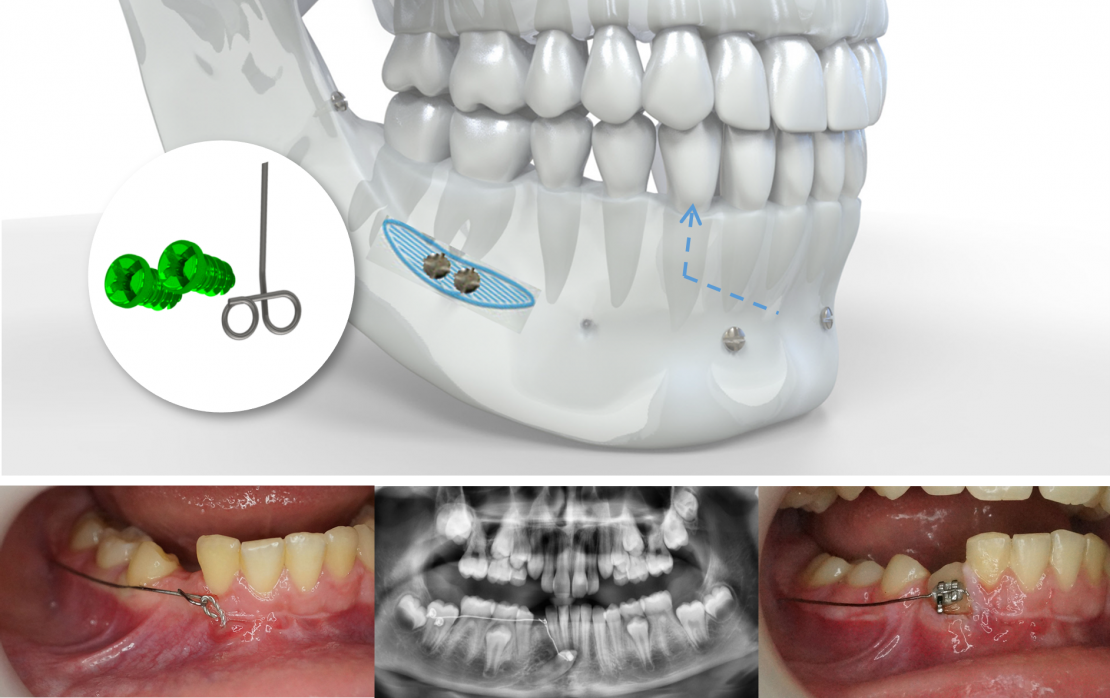

Site d'implantation

Ligne oblique externe mandibulaire

Le dégagement chirurgical de la couronne de la canine incluse vient d’être réalisé, la ligature accrochée au bouton collé à sa surface émerge à son emplacement naturel d’éruption. Le lambeau d’accès à la canine a été refermé et suturé.

Le bras du CT8 est activé vers le haut et vers l’extérieur pour une canine horizontale en vestibulaire des incisives, vers le haut pour une canine verticale retenue en position basse. Il est replié sur lui-même et accroché à la ligature reliée à la canine au niveau de son espace naturel d’éruption.

Les deux seules actions à réaliser par la suite seront :

1. Le raccourcissement de la ligature au fur et à mesure du déplacement de la canine.

2. Le contrôle de la direction de la traction et son réajustement éventuel lors de la même opération.

La canine fait éruption à son emplacement naturel. Si l’occlusion est acceptable par ailleurs, le CT8 peut agir d’une manière totalement autonome, sans autre appareil.